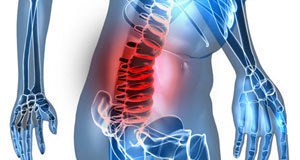

Kičmeni stub predstavlja temelj ljudske figure, potporu koja je čini stabilnom, a ljudima omogućava uspravan hod.

Sastoji se od pršljenova između kojih se nalaze diskovi koji funkcionišu kao amortizeri.

Na kičmeni stub se sa spoljne strane naslanjaju mišići, a unutar kičmenog stuba postoji kanal u kome se nalaze kičmena moždina i počeci kičmenih živaca.

Kičmeni stub se sastoji iz 3 dela: vratni (cervikalni), grudni (torakalni) i lumbalno-krsni (lumbosakralni).